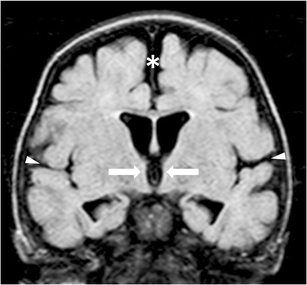

Fig. 3